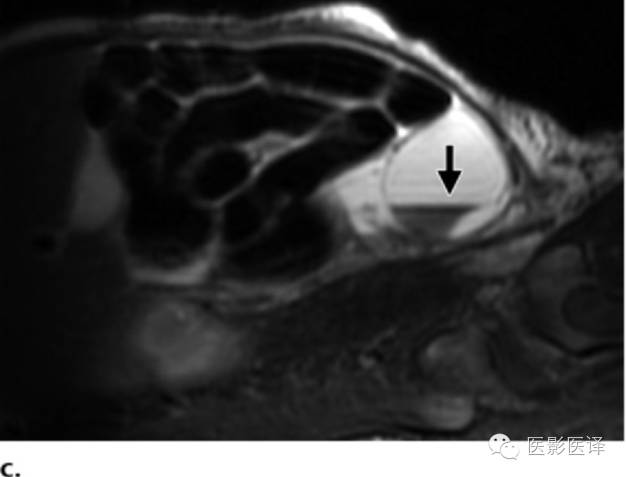

图8MR图像可清晰显示胎儿解剖。(a)稳态进动MR图像矢状位显示一囊肿内伴多发分隔(黑箭),该囊肿位于肝脏下缘、肾脏(K)前缘。可见脐静脉(uv;白箭)进入肝左叶。(b,c)稳态进动MR图像横断位显示胎儿子宫(图b中箭头所示)位于膀胱(B)后方,提示女性内生殖器,阴唇(图c中箭头所示),提示女性外生殖器。证实了女性生殖器存在也就可以支持卵巢囊肿的诊断;若显示为男性生殖器则可以将卵巢囊肿从鉴别诊断中排除。